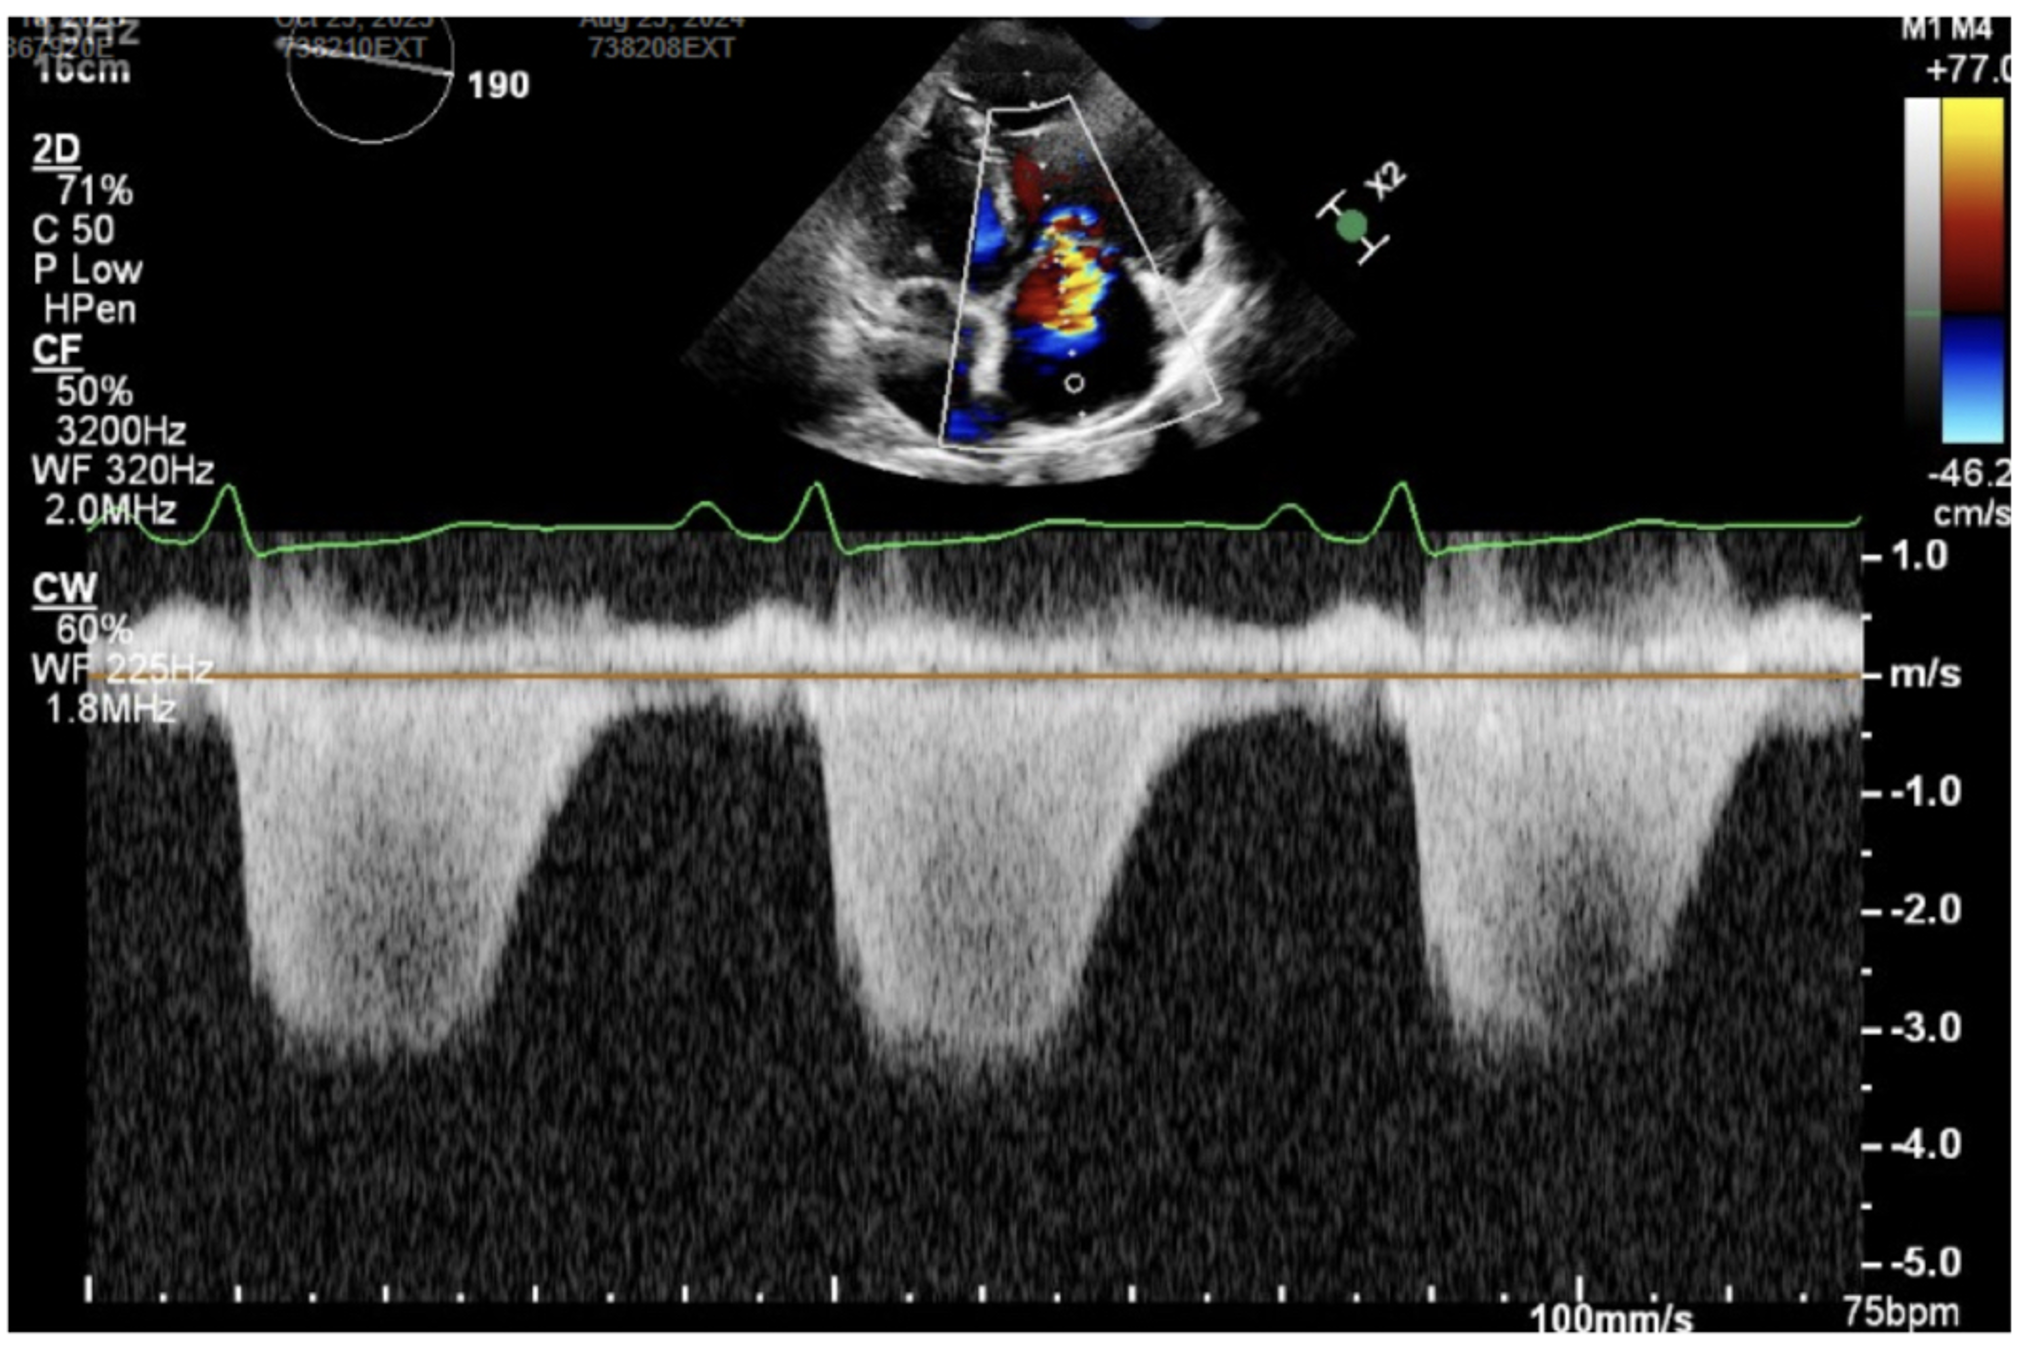

The picture above shows an apical four chamber view with color doppler over the right atrium (RA), showing a tricuspid regurgitation jet into the RA. The picture below shows continuous wave doppler through the tricuspid valve, which is a thick, well-defined curve signifying severe TR.

TAPSE (tricuspid annular plane systolic excursion) is assessed with M-mode over the tricuspid annulus in an apical 4-chamber view. This is a surrogate of RV function given the mechanics of RV contraction, which differs from LV contraction. >1.6 cm is a normal finding, while less than this indicates RV dysfunction.